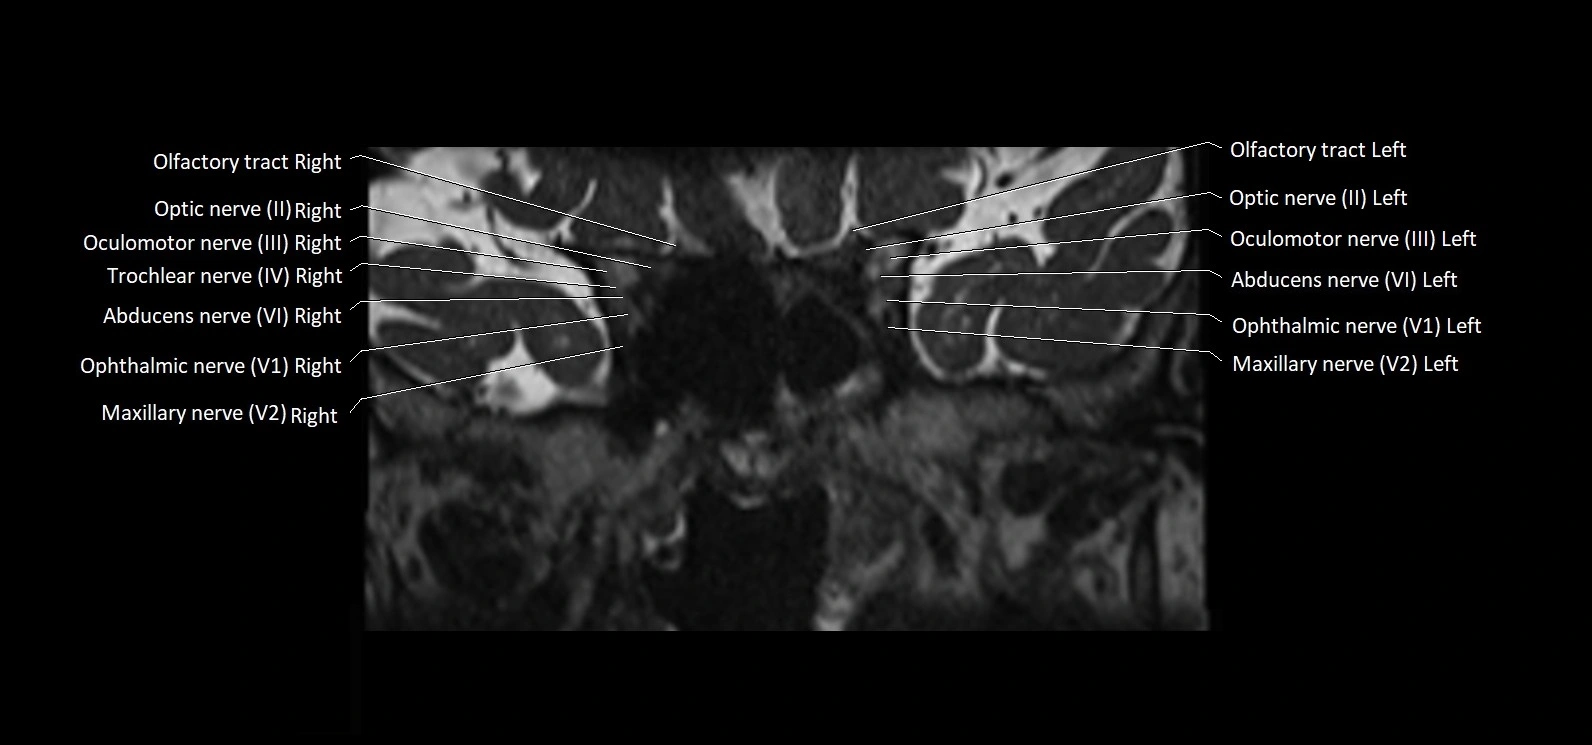

MRI Appearance

• The abducens nerve is a small, thin, linear structure

• Best visualized on high-resolution T2-weighted 3D MRI sequences (e.g., FIESTA or CISS)

• Seen as a hypointense (dark) line running from the brainstem at the pontomedullary junction, traversing the prepontine cistern, and entering Dorello’s canal under the petrosphenoidal ligament, then into the cavernous sinus, and finally the orbit

• May be challenging to visualize in standard MRI due to its small size

• Pathology may be inferred by absence, displacement, or enhancement of the nerve

MRI images

image